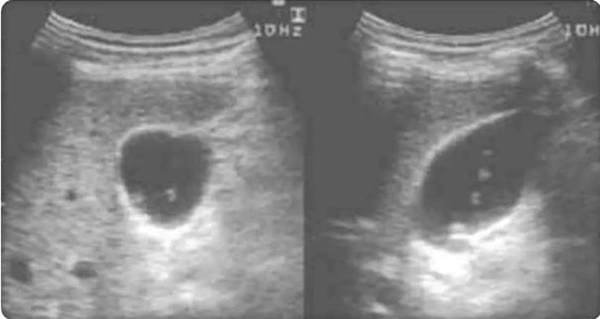

Hình ảnh siêu âm gan trái của ông Tạ khi bị sán lá gan nhỏ ăn mòn và gây áp xe (Ảnh bác sĩ cung cấp)

Siêu âm gan chỉ ra gan trái của ông gần như đã bị “đục rỗng”. Bởi các tế bào gan đều bị chúng tấn công, cả lá gan chẳng khác nào quả bóng lớn bên trong chứa đầy mủ. Khu vực viêm bị lan rộng ra xung quanh, nhất là vùng cơ bụng trước. Để điều trị áp xe gan, ông phải lập tức nhập viện làm phẫu thuật.